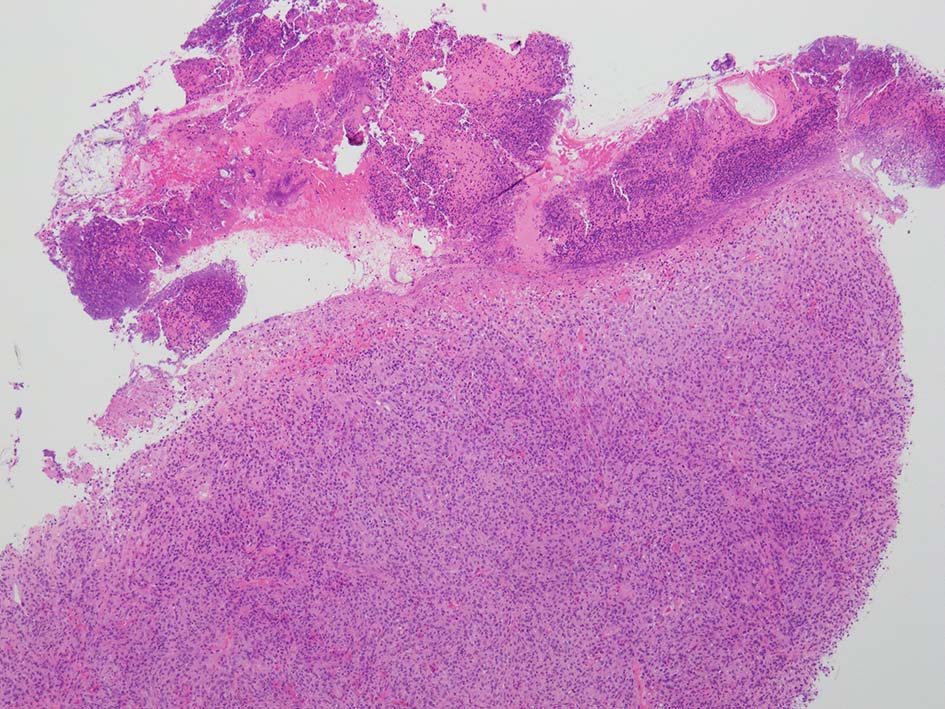

loupe像:表面に痂皮形成. 均等な組織像で,壊死や出血はみられない. 低倍ではspindle cellの密な増殖があるように見える. 拡大所見では, 類円形, 卵円形, ねじれた桿状の核, くびれ,勾玉様の核など不整形な核をもつ細胞が増殖している. クロマチンは繊細な傾向で, 核小体を1個もつ核が認められる. 高倍率10視野で 1-2個の核分裂像が数えられた.

大学病院に紹介され摘出手術がおこなわれた. 手術検体でも非典型的ではあるものの juvenile xanthogranuloma に矛盾しなかった。

手術検体でも、明瞭な泡沫細胞は指摘できませんでしたが、Tuton型巨細胞が少数確認できた. 免疫染色の結果も、juvenile xanthogranuloma を支持する所見であった。 全身精査を行ったところ、他に病変は見当たらず、単発性であることが確認できた。(大学病理診断担当先生からの報告)

JXGの他のvariantとして、早期型と後期型があり, 早期型は、古典型にみられる脂質空胞をもたないmononorphicな組織球が密に増殖するものである。後期型は、泡沫組織球や巨細胞の病巣を伴う紡錘形細胞の渦状増殖が見られる. また, リンパ球や好酸球の混在も認められる。